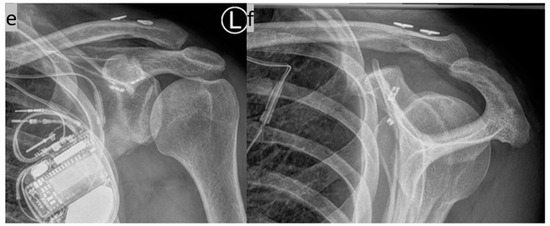

2. Surgical Technique